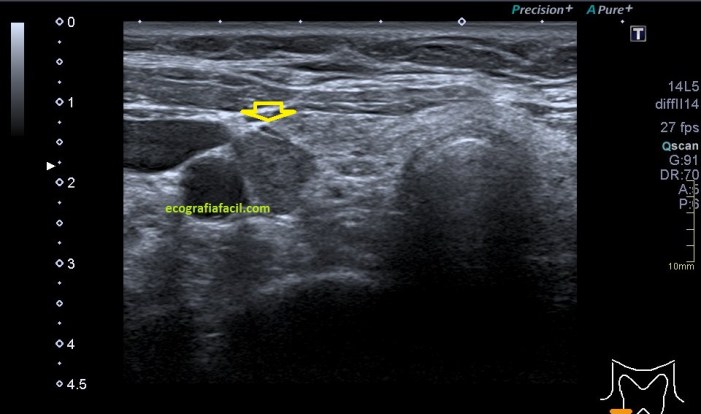

En algunas ocasiones podemos encontrarnos esto:

Compara la imagen 1 y la 2, grábala en tu memoria fotográfica. Ambas son unas imágenes en corte longitudinal del teste derecho de dos pacientes distintos.

Una vez que hemos encontrado la lesión, es momento de estudiarla detenidamente, su aspecto, tamaño bordes y vascularización son vitales para que la radióloga pueda efectuar un informe.

La imagen 3 y 4 son parte estudian en eje largo y corto las medidas de la lesión en los tres ejes del espacio, en ocasiones, podemos tener más de una lesión. Siempre super atentos si las lesiones son intra o extratesticulares.